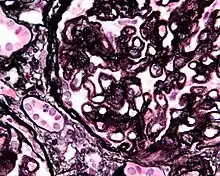

Micrograph showing glomular basement membrane spike formation in membranous nephropathy. Jones stain.